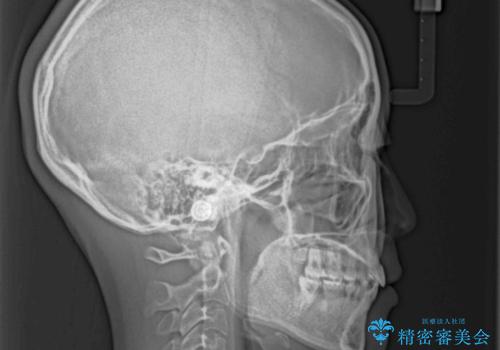

当初はインビザラインによる矯正治療をご希望でしたが、正中を合わせたいことや、口元の突出感を改善したいことから、ワイヤー矯正を強く推奨しました。

治療期間は2年に満たず、スッキリとした口元に仕上がりました。